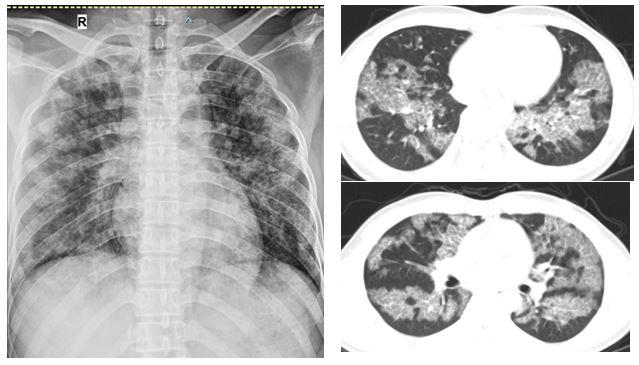

Tuy nhiên, kết quả chụp cắt lớp vi tính ngực cho thấy bệnh nhân tổn thương lan tỏa hai phổi, đây chính là nguyên nhân gây khó thở. Bệnh nhân được nội soi phế quản lấy dịch rửa phế quản làm xét nghiệm. Dựa trên các dữ liệu lâm sàng, xét nghiệm dịch phế quản và phim chụp cắt lớp vi tính ngực, người bệnh được chẩn đoán “Bệnh tích protein phế nang” và được chỉ định rửa phổi.

| Hình ảnh tổn thương lan tỏa hai phổi của người bệnh trước khi rửa phổi. |